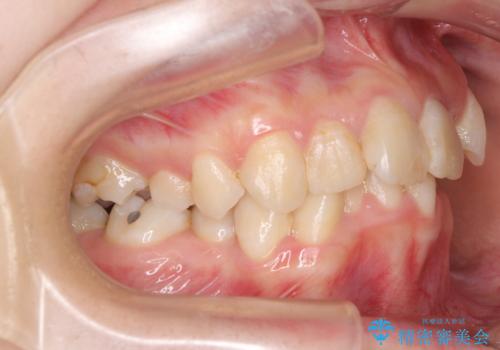

- 内側に倒れ込んだ歯や下の前歯が隠れてしまうほどの咬み合わせを改善したいとのことで来院された患者様です。

下顎の叢生を解消するために抜歯が必要であり、奥歯の咬み合わせや口元の印象から、上顎も同様に抜歯と判断し、上下左右の第1小臼歯4本抜歯してワイヤー装置にて矯正治療を行うこととしました。

咬み合わせが深く、そのままでは上顎の抜歯スペースが閉じきらない可能性があったため、治療初期から深い咬み合わせを改善させるように試みました。